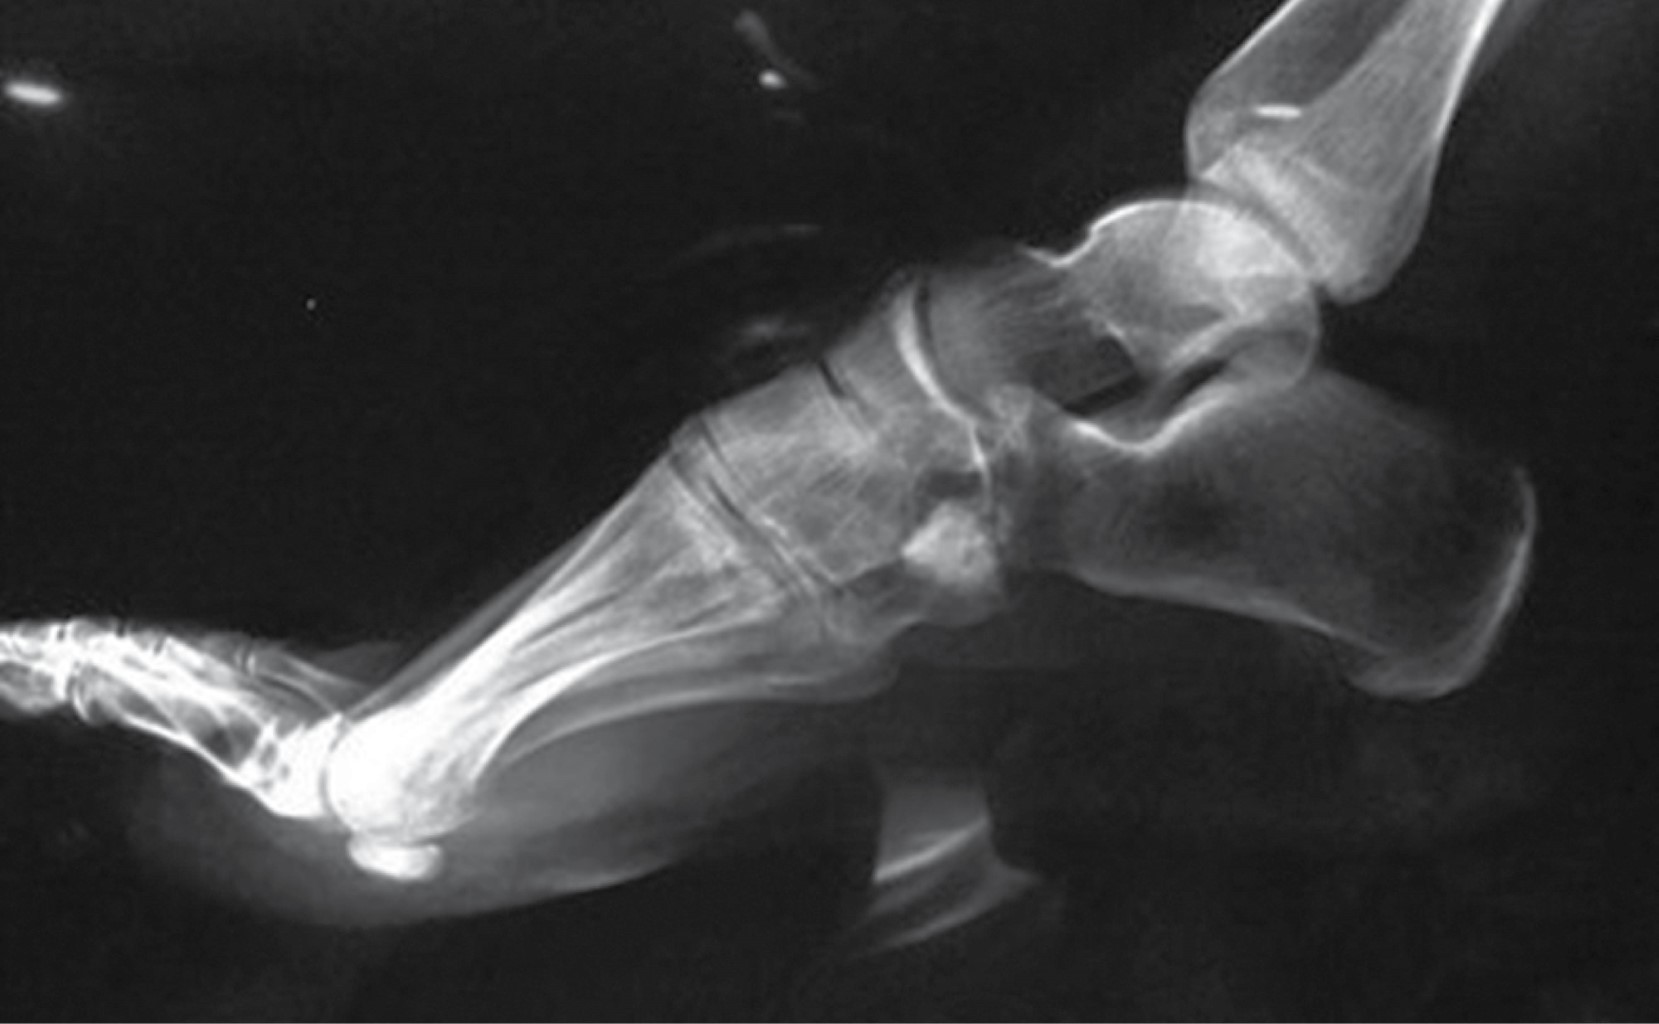

En las radiografías dorsoplantar y lateral de pie derecho se observa injerto óseo en el centro de una lesión en cuboides, radiotransparente, heterogénea, multilobulada, con bordes irregulares que sobrepasan la cortical lateral, multilobulados (Figuras 2 y 3).